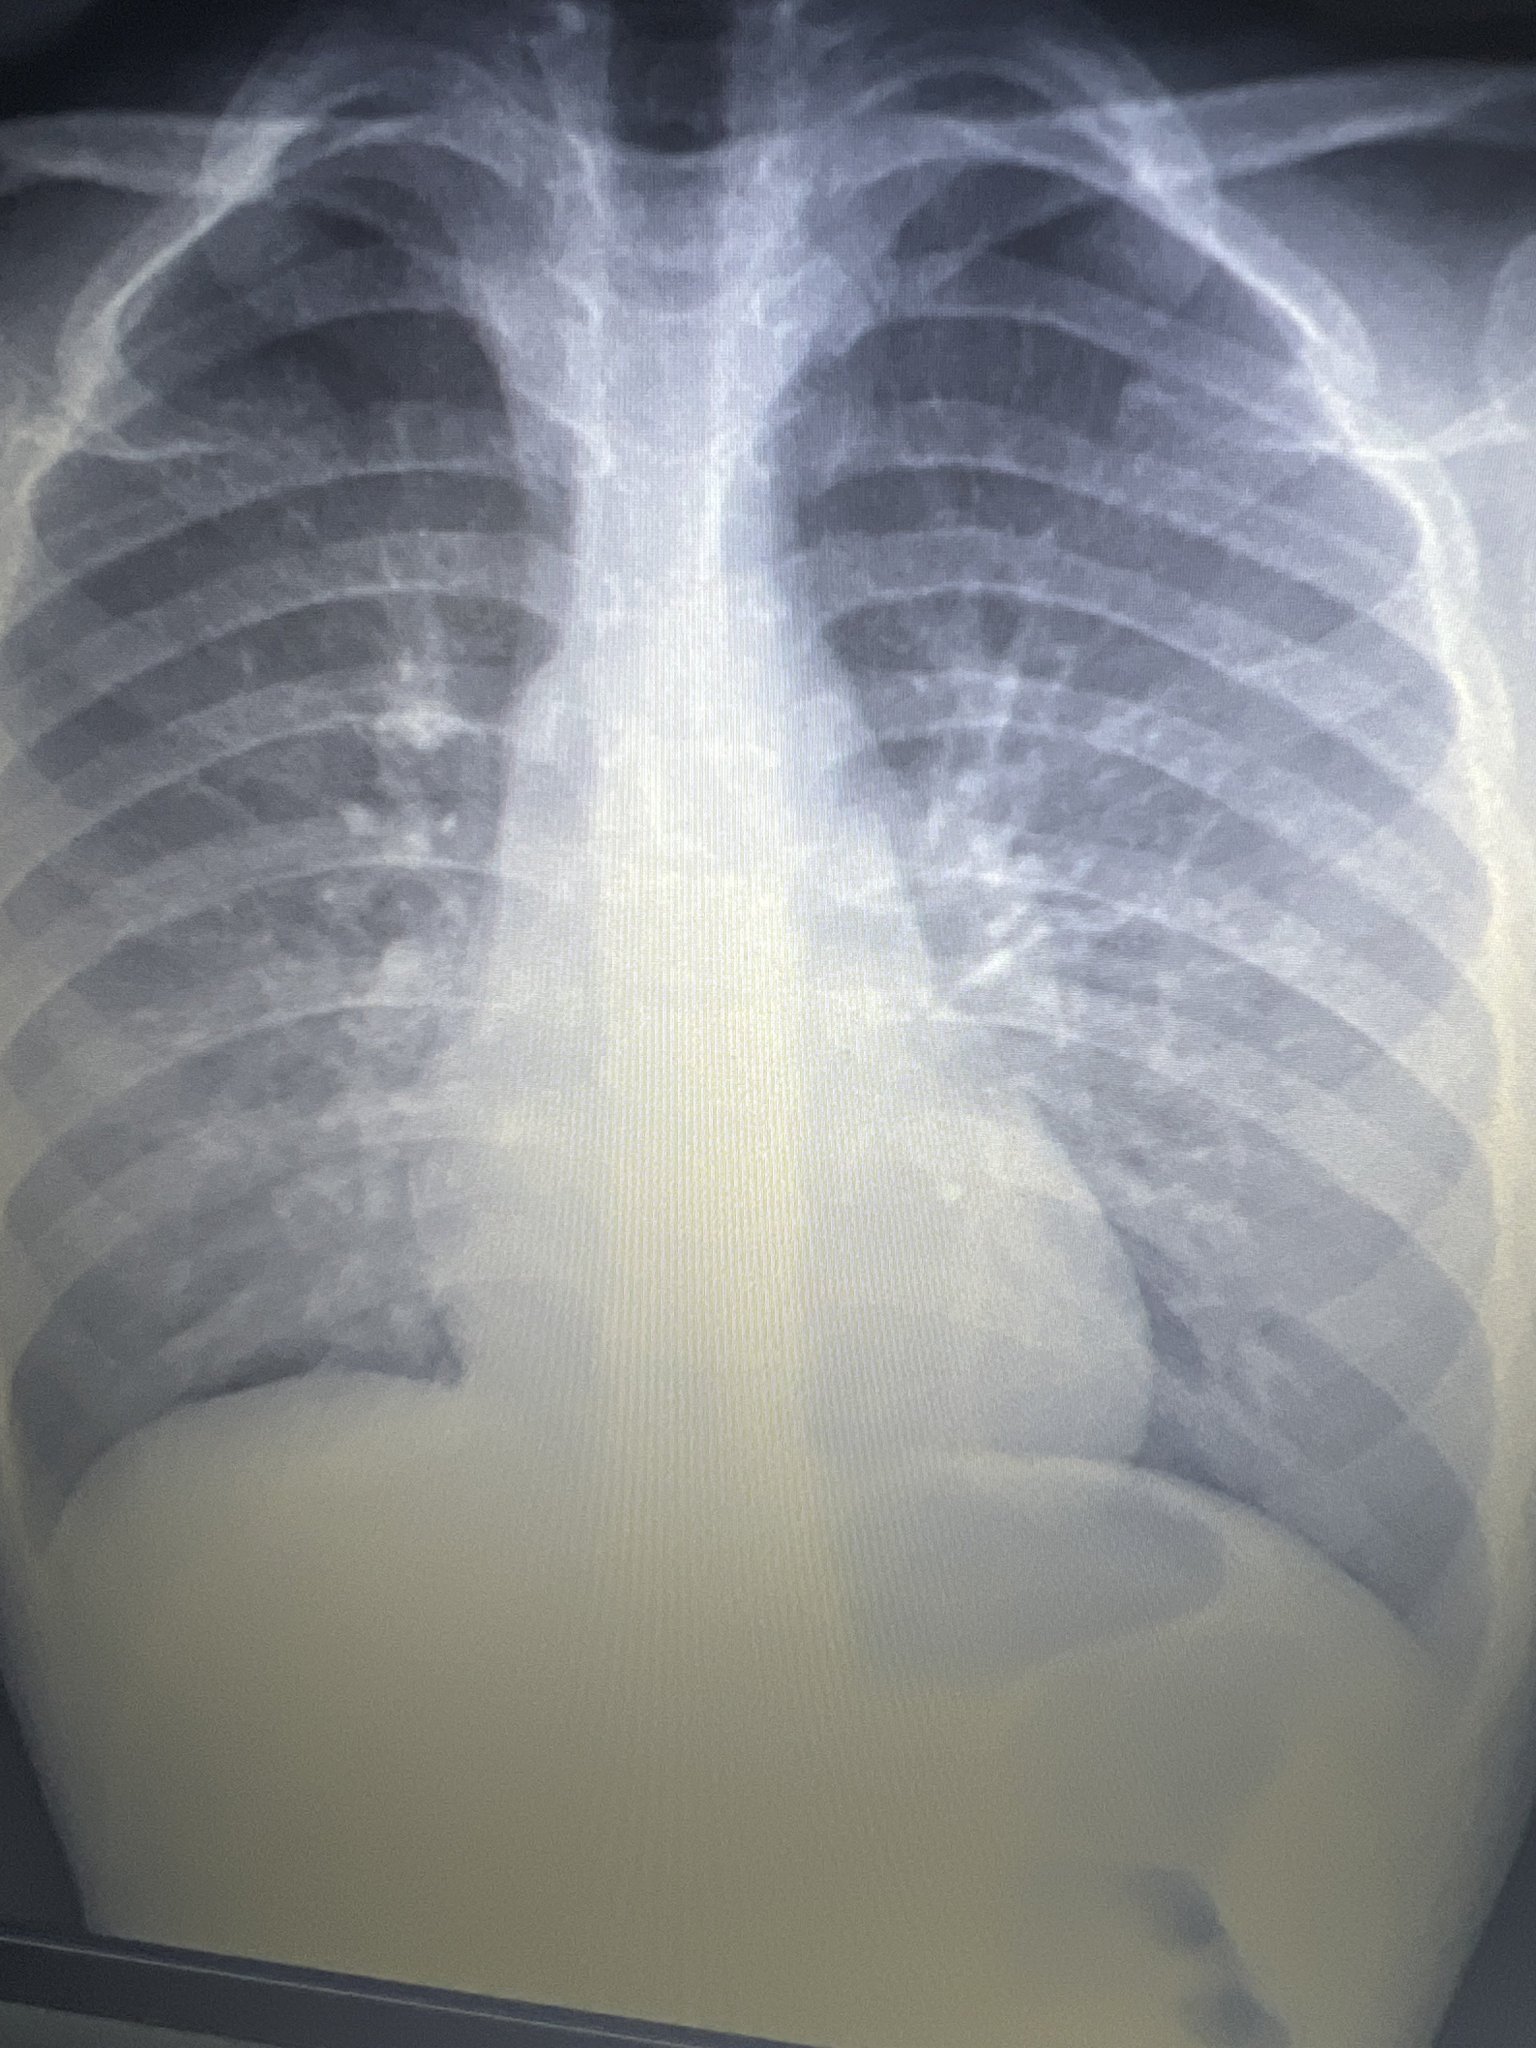

Здравейте, д-р Янкова! Ще може ли да коментирате рентгеновата снимка на сина ми, която е правена след изкаран Ковид и Грип А. Снимката е правена на 26 януари и пи АБ до преди 10 дни, но от два дни детето е с температура около 37-37,7, слаба кашлица, хрема и нощно изпотяване и треска при ниска Т около 37 градуса. Целият става мокър вечер. Вчера му пуснахме изследвания, които според мен (до колкото разбирам) говорят за бактериална инфекция. Ще ви прикача рентгена и изследванията. Моля Ви за съвет, защото вече се виждам в чудо с това болно дете от 1 месец! Притеснява ме да не би да е бил с пневмония и да не се е доизлекувал...... т.е. да не е разчетена правилно снимката, а ме е страх за няма месец да го снимам два пъти. АБ беше Клацид от 250 за 7 дни.

Здравейте, на снимката и изследванията няма нищо притеснително. Всички тези оплаквани и симптоми, които има, са най-вероятно вследствие на постковид синдром. След 2 седмици ще отзвучат.